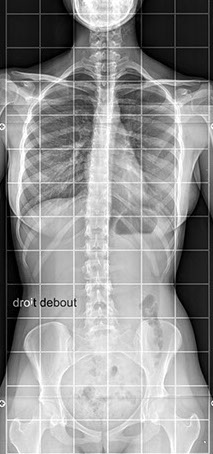

Elle peut être réalisée sur tout le corps et permet avant tout l’étude des os,

Pour les os et articulations : des fractures, de l’arthrose, des malformations

Elle utilise les rayons X, consistant à impressionner un film qui sera plus ou moins noirci selon l’organe radiographié : ainsi les os apparaîtront blancs et l’air noir ; les tissus mous seront de différentes nuances de gris.

Dans notre cabinet, la technique est numérisée et la surface sensible est en fait un capteur et non un film, ce qui permet de modifier le contraste après avoir pris le cliché et d’agrandir certaines zones pour mieux voir.